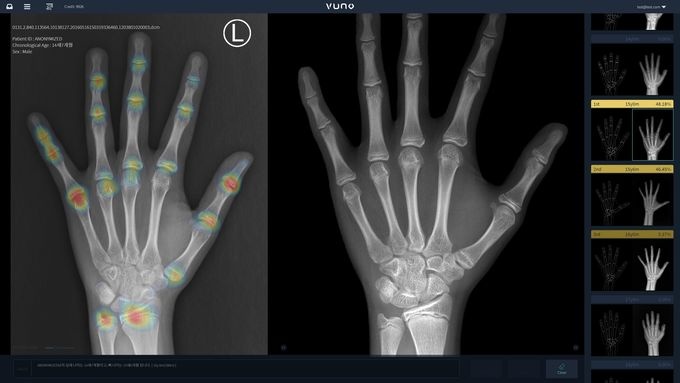

µ¥Àϸ®¸Þµð ¹Ú´ëÁø ±âÀÚ] ´ë±¸ÆÄƼ¸¶º´¿ø(º´¿øÀå ±è¼±¹Ì °ñ·ë¹Ù ¼ö³à)Àº ÃÖ±Ù Áø´Ü Á¤È®µµ Çâ»óÀ» À§ÇØ ÀΰøÁö´É ÀÇ·á±â±âÀÎ ºä³ë¸Þµå º»¿¡ÀÌÁö(VUNO Med®-BoneAge)¸¦ µµÀÔÇß´Ù.

ÇØ´ç ÀÇ·á±â±â´Â ¼ö°ñ(¼Õ ¹× ¼Õ¸ñ»À) ¿¢½º·¹ÀÌ ¿µ»óÀ» ÀÚµ¿ ºÐ¼®ÇÏ°í ¼öÃʳ» °¡Àå À¯»çÇÑ °ñ¿¬·ÉÀ» ÃÖ´ë 3¼øÀ§±îÁö Á¦½ÃÇØ ÀÇ·áÁøÀÇ Áø´ÜÀ» µ½´Â´Ù.

¶ÇÇÑ ÀΰøÁö´É ºÐ¼®°á°ú¸¦ ¹ÙÅÁÀ¸·Î ¿¹Ãø ¼ºÀåŰ µî ¼ºÀå Á¤º¸¸¦ ´ãÀº ¸®Æ÷Æ®¸¦ Á¦°øÇØ È¯ÀÚ¿¡°Ô º¸´Ù À¯¿ëÇÑ ¼ºÀå °ü·Ã Á¤º¸¸¦ Á¦°øÇÑ´Ù.